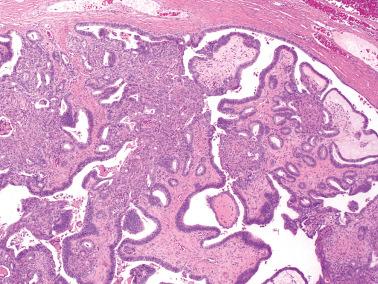

Gross features ( figs. 14.51 14.52 )

• CCCs are typically unilocular or less often multilocular cysts with polypoid intraluminal masses to nonspecific solid or solid and cystic masses. Some cysts may be grossly recognizable as endometriotic. CCCs with an adenofibromatous component may exhibit the gross features of the latter, as noted above.

Fig. 14.52, Clear cell carcinoma arising in an adenofibroma. The tan brown component was invasive clear cell carcinoma. Background adenofibroma was represented by the white tissue (right).

Microscopic features of benign and borderline clear cell tumors ( figs. 14.53–14.56 )

• These tumors are almost always adenofibromatous and must be thoroughly sampled to exclude foci diagnostic of CCC that may be limited in amount.

• Borderline adenofibromas contain atypical epithelium that is usually of clear or hobnail type. If carcinomatous epithelium without invasion is present, the tumor is a borderline adenofibroma but such a tumor should be thoroughly sectioned to exclude invasion, especially if the epithelial proliferation is striking. Closely packed glands without stroma or only minimal intervening stroma should raise concern for CCC.